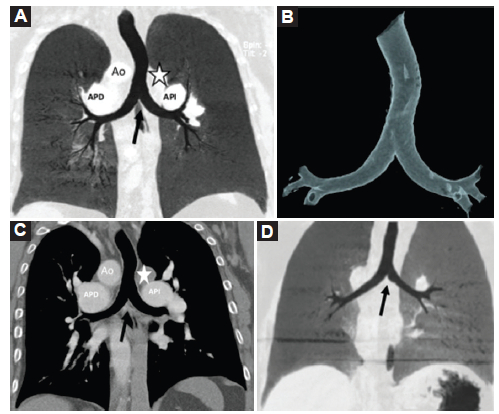

Alteraciones vasculares

La alteración más frecuentemente asociada es la interrupción de la VCI retrohepática con continuación como vena ácigos o hemiácigos, hallazgo que se observa en todos los casos (Fig. 5). Esta alteración puede ser sugerida por la radiografía de tórax, como en el caso 1, en el que se observó ausencia de la VCI en el sector posteroinferior de la silueta cardiaca en el enfoque lateral y el cayado de la ácigos prominente en la proyección frontal (Fig. 6).

La VCI infrarrenal discurrió normalmente a la derecha de la aorta, hasta la desembocadura de ambas venas renales en los casos 3 y 4. En el caso 1 presenta un recorrido a la izquierda de la aorta. Luego continuó como vena ácigos aumentada de tamaño, formando un prominente cayado de la ácigos, a la derecha en el caso 3 y a la izquierda en los casos 1 y 2 (Fig. 7).

El retorno venoso pulmonar y sistémico puede ser anómalo y tiene una gran variedad de presentaciones. En el caso 1 se observó una anomalía parcial del retorno venoso pulmonar, la vena pulmonar superior derecha drenando a la aurícula derecha (Fig. 8A), asociado a un retorno venoso sistémico anómalo con la vena cava superior e inferior drenando ambas a la aurícula izquierda y estableciendo así un shunt pulmonar del retorno sistémico (Fig. 8 B y C). En el caso 3 se observaron dos venas cava superiores (derecha e izquierda); que drenan a sus respectivas arterias pulmonares (Fig. 8 D) determinando una alteración del retorno venoso sistémico.